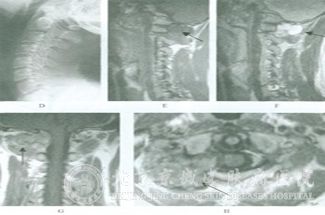

北京京城皮肤医院指出:局限性皮肤神经纤维瘤的组织形态的典型病例由交织状排列的梭形*束组成,*边界不清,*质淡嗜伊红色,*核深染,两端尖,波浪状或弯曲状,部分病例中于瘤之间可见绳索样的胶原纤维,瘤和胶原束之间为少至中等量的黏液。